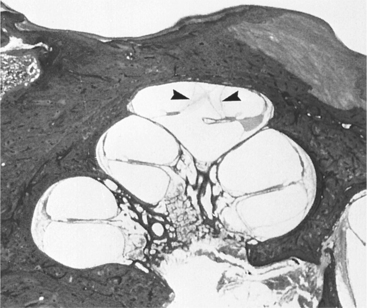

Pathogenesis.: Although the pathophysiologic mechanism involves a disruption of homeostasis of inner ear fluid, the mechanism and the pathophysiology of the symptoms are uncertain. Endolymphatic hydrops may be an epiphenomenon rather than directly responsible for the symptoms. Deficits are related to the volume and pressure changes within closed fluid systems. The increase in the volume of endolymph causes the membranous labyrinth to progressively dilate until the wall makes contact with the stapes footplate and the cochlear duct fills the entire scala vestibuli, causing both vestibular and cochlear dysfunction. Fig. 38-14 shows the cross view of the canal and the changes that can occur with increased pressure. Distension of the otoliths can put pressure on the ampulla, creating the sensation of spinning that is characteristic of acute unilateral dysfunction. The mem- brane that separates the endolymph from the perilymph may rupture, and there is a leakage of potassium into the endolymph that may result in palsy of the vestibular nerve fibers.

Figure 38-14 Cross-section of human cochlea demonstrating endolymphatic hydrops in a patient with Menière’s syndrome. Note the distension of Reissner’s membrane into the scala tympani in the apical turn of the cochlea (arrowhead). (From Cummings CW, Haughey BH, Thomas R, et al: Cummings otolaryngology: head and neck surgery, ed 4, St Louis, 2004, Mosby.)